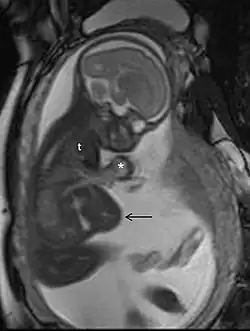

Ressonância magnética

A ressonância magnética (RM), sem meio de contraste em RM, não está associada a riscos para a mãe ou o feto e, juntamente com a ultrassonografia médica, é a técnica de escolha para exames de imagem na gravidez.[1]

Usos comuns

A RM é frequentemente utilizada em gestantes com dor abdominal e/ou dor pélvica aguda, ou em casos suspeitos de doença neurológica, doença placentária, tumores, infecções e/ou doença cardiovascular.[3] Os critérios de uso apropriado do Colégio Americano de Radiologia dão nota ≥7 (geralmente apropriado) para RM sem contraste nas seguintes condições: